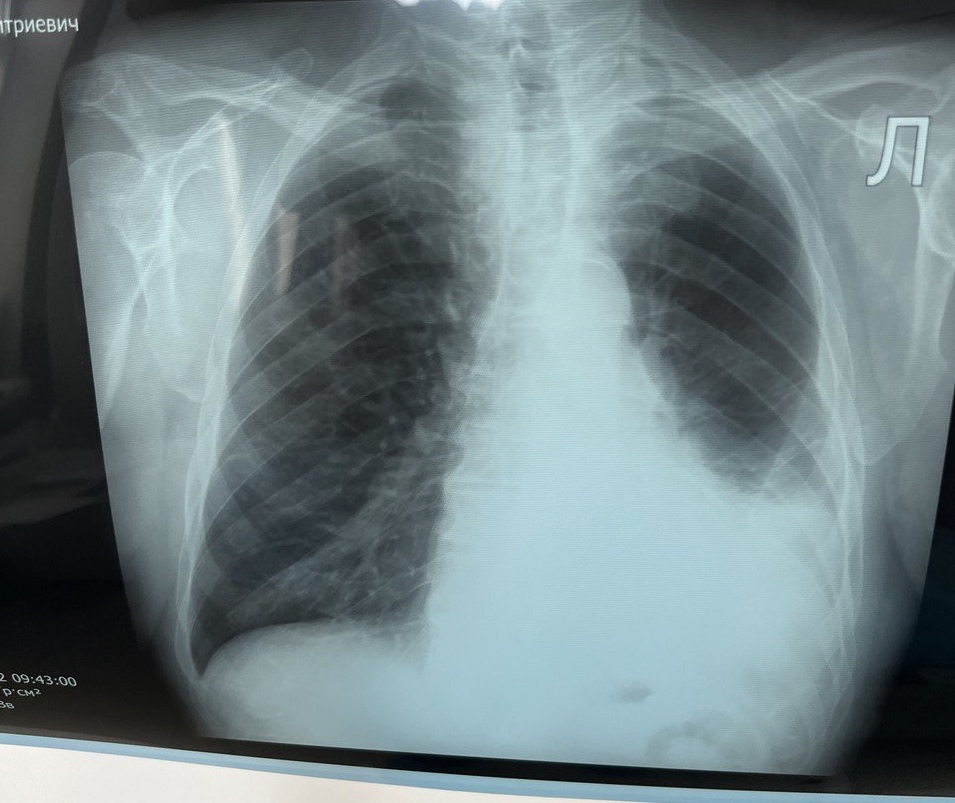

Контрольная рентгенография органов грудной клетки, выполненная в апреле 2022 г. показала положительную динамику, в частности, уменьшение гидроторакса до уровня 6-го ребра.